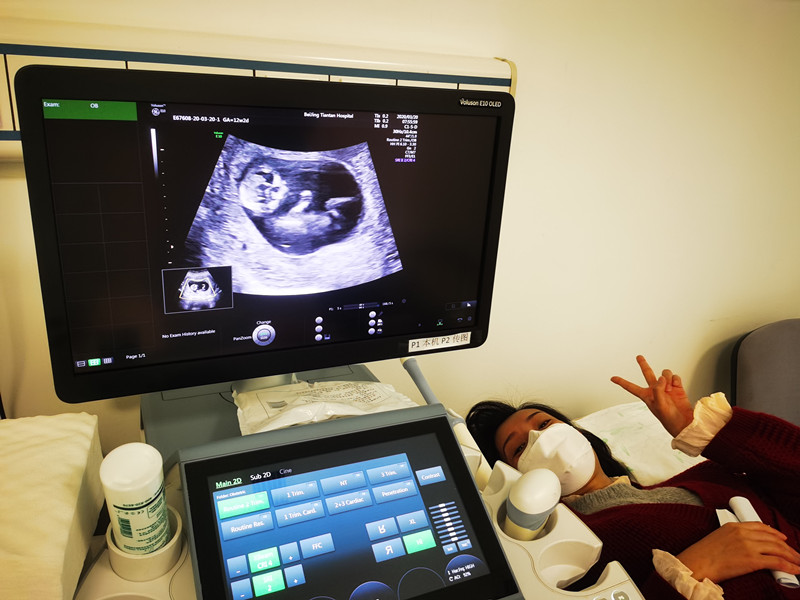

“你看,这是他的头,这是小手,还在动……”3月20日,是北京支援武汉医疗队在武汉工作的第54天,来自北京天坛医院的队员袁磊第一次通过B超影像,见到了自己的宝宝。

医院各级领导对支援武汉医疗队队员和家人的生活十分关心,特别安排护理部人文关怀小组组长苏娅丽等全程照顾。早上8点,杜晓彤在母亲的陪伴下来到北京天坛医院超声科,安静地躺在检查床上。随着超声科副主任医师王立淑的操作,显示屏上,一个小小的胎儿形象清晰地显示出来。

“袁磊,看看你们家宝宝,可爱吗?”苏娅丽用手机拍摄下显示屏上的画面,伸手、踢腿、翻身,这个87天的小生命似乎听到了外面的召唤,用各种动作回应大家的召唤,每一个动作都会引起大家的笑声。检查室里只有躺在床上的杜晓彤看不到屏幕,一脸茫然。